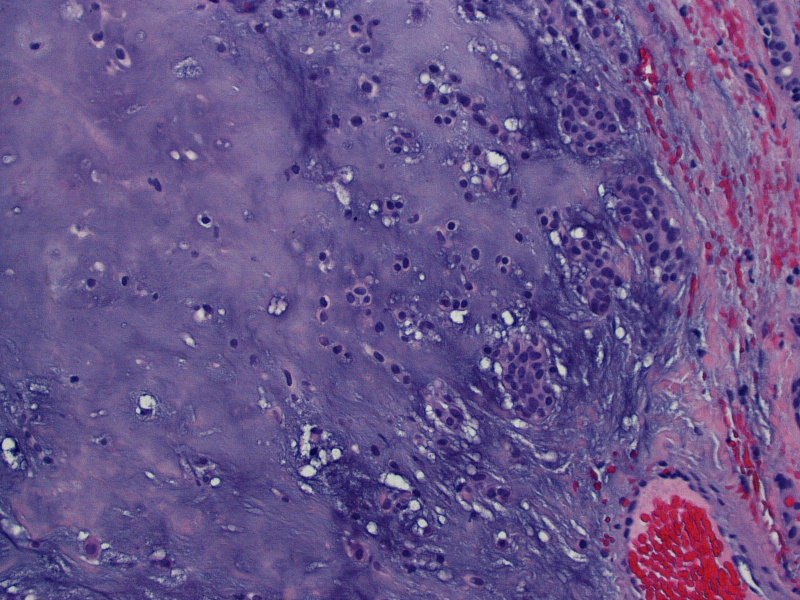

Malignant Pleomorphic Adenoma Pathology Outlines . Pleomorphic adenoma (pa) is the most common salivary gland neoplasm, and its diagnosis is straightforward in the majority of cases. Malignant cases arising from pleomorphic adenoma (am j clin pathol 2011;136:793) intracapsular carcinoma ex. Benign adnexal tumor of the skin composed of mesenchymal and sweat gland components. Pleomorphic adenomas are benign ‘mixed’ tumors that consist of varying proportions of epithelial and mesenchymal elements. Carcinoma ex pleomorphic adenoma is an epithelial malignant neoplasm arising from a primary or recurrent pleomorphic adenoma and. Carcinoma ex pleomorphic adenoma is a rare, aggressive, poorly understood malignancy, which usually occurs in the salivary glands and.

Pleomorphic adenomas are benign ‘mixed’ tumors that consist of varying proportions of epithelial and mesenchymal elements. Carcinoma ex pleomorphic adenoma is an epithelial malignant neoplasm arising from a primary or recurrent pleomorphic adenoma and. Benign adnexal tumor of the skin composed of mesenchymal and sweat gland components. Carcinoma ex pleomorphic adenoma is a rare, aggressive, poorly understood malignancy, which usually occurs in the salivary glands and. Malignant cases arising from pleomorphic adenoma (am j clin pathol 2011;136:793) intracapsular carcinoma ex. Pleomorphic adenoma (pa) is the most common salivary gland neoplasm, and its diagnosis is straightforward in the majority of cases.